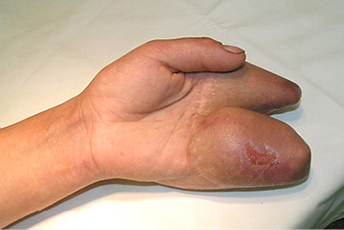

5 pav.

6 pav

7 pav.

8 pav.

Vaizdas po I rekonstrukcijos etapo. Prigijęs kirkšnies lopas vėliau atskirtas nuo donorinės vietos ir perskeltas tarp III ir IV pirštų, suformuojant dviejų pirštų kompleksus. Stebimas minkštųjų audinių perteklius, ypač ties IV pirštu, kur buvusi lopo „kojytė“ ir darbiniame suformuoto piršto paviršiuje atsivėrusi opelė (5–8 pav.)